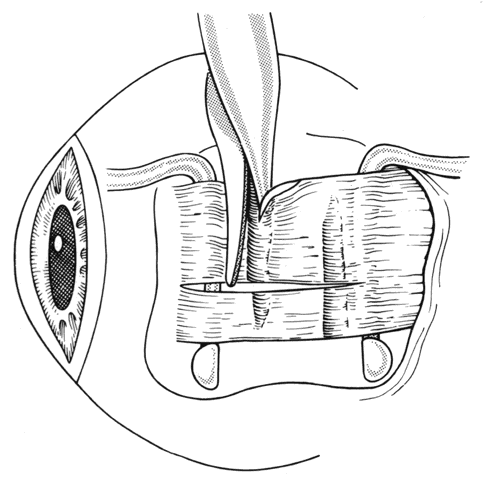

To detect and disrupt adhesions between the underside of the rectus muscle and the globe, or attachments between the lateral rectus and the inferior oblique muscle, a Jameson muscle hook is slid posteriorly.37 If an adhesion is encountered, it can usually be broken by gently disrupting the adhesion with a second Jameson hook (Figs. 23 and 24). If additional adherent tissue remains near the insertion, it should be removed prior to placement of sutures at the insertion of the tendon (Fig. 25).

Fig. 23. A Jameson muscle hook is placed under the insertion.

Fig. 24. Adhesions between the underside of the muscle and the sclera can be broken by gently passing the Jameson hook posteriorly. Failure to free up these adhesions will reduce or eliminate the effect of recession of the muscle.